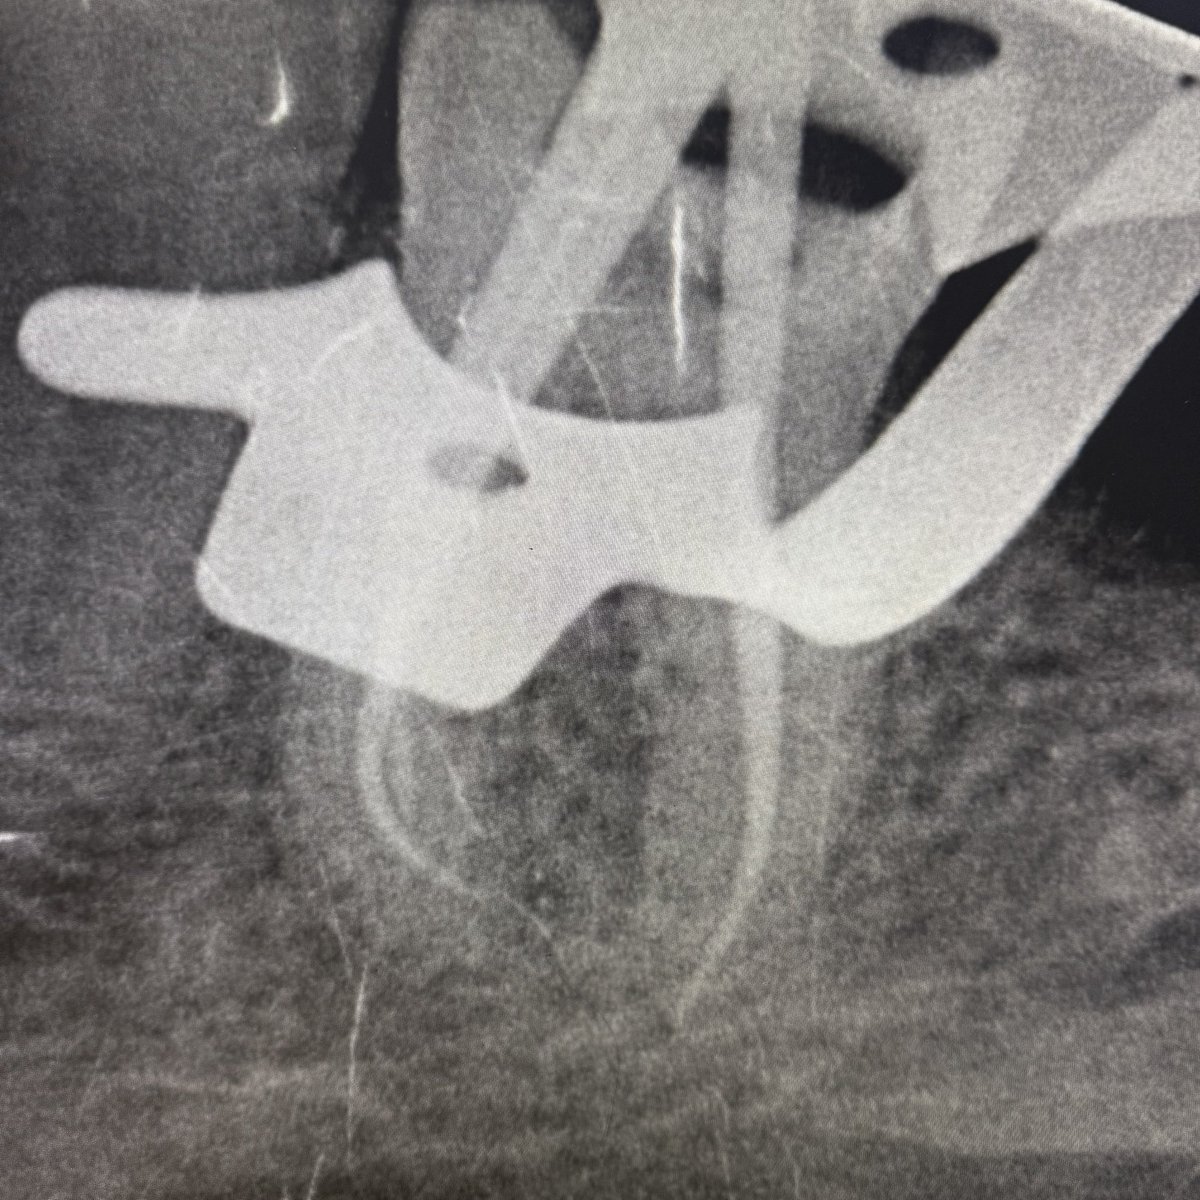

Finalllyy Sep&October’s case 🤩

Cc :“i have severe pain on my upper anterior tooth while drinking cold“

MH : ASA II

DH : multiple Extractions

after IOE : #12 was diagnosed“Asymptomatic irreversible pulpitis with symptomatic apical periodontitis“

Tx : RCT,post&core and crown